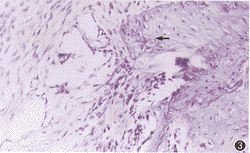

1.实验组:①术后1周,牙槽骨人工缺损周围可见牙槽骨和牙周膜组织变性坏死及大量炎性细胞浸润(图1),其间可见残存的变性组织。②术后2周,骨缺损处炎性细胞渗出明显吸收,成纤维细胞和毛细血管生长活跃,周边有骨样组织和少量骨组织形成(图2)。③术后3周,新生的骨组织范围扩大,钙盐沉积增多(图3)。④术后3个月,缺损处几乎被新生骨组织充填,仅存少许纤维组织(图4),周边可见骨小梁形成。

图3 光镜下新生骨向中心堆积(↑,HE×40)